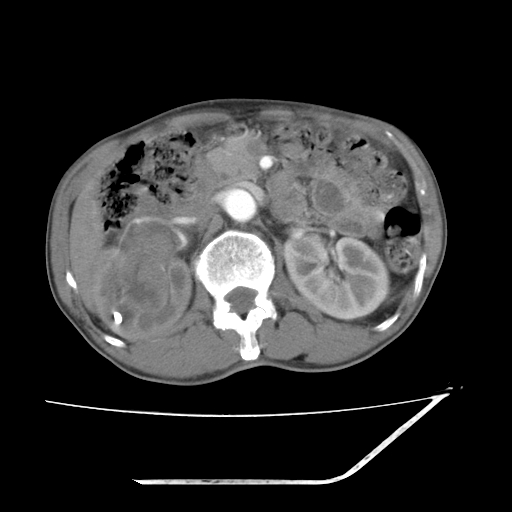

增强

考虑右肾盂癌,肾动脉受侵,右肾功能减退,右肾盂输尿管积水,管壁增厚,考虑种植转移,应该把下面扫完的

支持右侧肾盂癌伴肾静脉瘤栓形成可能性大,右肾结石.肝右叶后段低密度影,不除外转移.

考虑右侧肾盂癌。右侧输尿管扩张未扫描完。

右肾盂癌,肾动脉受侵,右肾盂输尿管积水,管壁增厚,考虑种植转移

右肾盂移行细胞癌并右输尿管中段转移.肾积水.

支持 右侧肾盂癌伴肾静脉瘤栓形成可能性大,右肾结石;肝右叶后段低密度影,不除外转移。

1.右侧肾盂癌伴肾盂积水。

2.肾脏功能减退,原因有:(1)肾动脉受侵。(2)肾静脉受侵(3)肾积水,等。本例,肾动脉显影较好,但受压明显;肾静脉无明显显示,受压或静脉癌栓,下腔静脉腔内未见明显充盈缺损。

3.右侧上段输尿管扩张,原因:(1)积水所致;(2)种植。